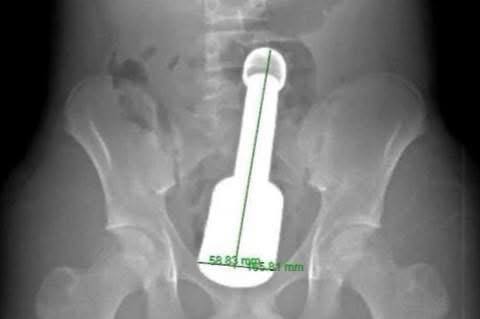

Thiếu nhi 15 tuổi ở Hà Nội được gia đình đưa vào viện cấp cứu trong đêm, với biểu hiện đau dữ dội vùng hạ vị. Hình ảnh chụp X-quang cho thấy có dị vật kim loại kích thước lớn mắc kẹt trong trực tràng.

Nam bệnh nhân N.K.N. (15 tuổi, Hà Đông, Hà Nội) được gia đình đưa vào viện cấp cứu trong đêm, với biểu hiện đau tức dữ dội vùng hạ vị. Kết quả chẩn đoán hình ảnh xác định một dị vật kim loại kích thước lớn mắc kẹt sâu trong trực tràng, gây chèn ép các cơ quan vùng chậu.

Hình ảnh chiếc chày được lấy ra từ hậu môn của bệnh nhân.

Sau hơn 45 phút, chiếc chày dài 18cm với đường kính 6cm đã được rút ra hoàn toàn qua đường hậu môn thành công.